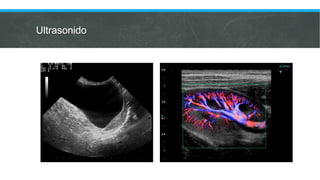

Ultrasonido

Ultrasonido escrotal

 Dificultad clínica para delimitar la

anatomía testicular.

 Masa testicular que no transilumina.

 Sospecha de patología testicular

asociada.

 Hidrocele asociado con dolor

testicular.

 Hidrocele adquirido.

Ultrasonido Doppler testicular

 Sospecha de hidrocele secundario

a varicocele o torsión testicular.

Ultrasonido abdominal y escrotal

 Hidrocele abdominoescrotal.